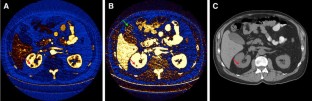

Technical improvements in the acquisition and display of dual-energy computed tomography (DECT) have made this technique increasingly applicable to clinical practice, particularly in the setting of oncologic imaging. DECT allows for qualitative and quantitative analysis of tissue composition beyond the standard anatomical evaluation possible with single-energy computed tomography. For example, DECT can be used to interrogate iodine and calcium concentrations and to increase iodine signal, which makes many pathologic processes more conspicuous and provides improved understanding of internal structure within mass lesions. A working understanding of common postprocessing DECT displays will allow radiologists to maximize the additional diagnostic information available in DECT examinations. In this article, we describe common strategies for DECT interrogation by organ system, which may improve the conspicuity and understanding of suspected malignancies.

Fig. 1